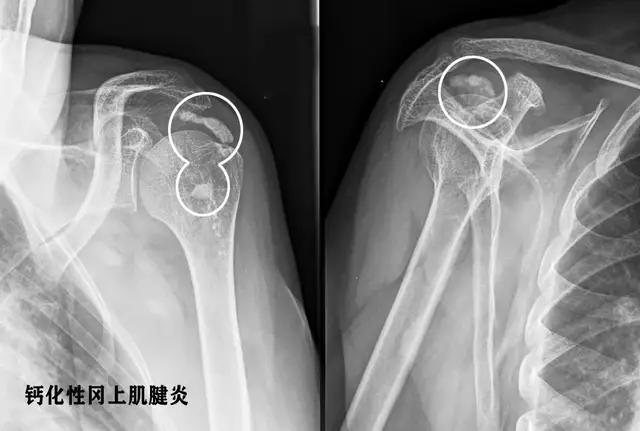

●钙化性冈上肌腱炎:这个疾病起病的时候往往特别急骤,有的时候患者在发病前一天有过度劳累或者是肩部运动的病史。睡了一觉以后,第2天早上出现剧烈的肩部疼痛,而且会伴有肩部的肿胀,患者不敢做任何的肩部动作,否则会疼痛难忍,到医院的时候会特别的急,想要要求医生尽快的帮助去控制住疼痛。

对于这样来医院比较急的肩痛患者,往往要首先考虑是否存在着钙化性冈上肌腱炎,要首先给予患者进行最简单的肩关节普通x线平片检查,费用比较低,而且出片比较快,要首先判断是否存在肩关节周边的钙化。

为什么会出现这种疾病的原因,还不是特别的明确,一般这个钙化不是一天形成的,是日积月累慢慢形成的,但是在形成的过程中往往不是特别的疼痛,患者可能偶尔会有肩关节的疼痛,但是休息之后就能缓解。慢慢的这些钙化会吸收,越是到了吸收的阶段,疼痛往往会越明显,而且有可能过度的使用肩关节,刺激到了钙化局部的病灶,也会导致肌肉的肩关节疼痛。

治疗:大部分的钙化性冈上肌腱炎患者,可以通过保守治疗来缓解,具体的保守治疗与前面几种疾病的保守治疗措施是差不多的。最近有一种新的技术,对于钙化性冈上肌腱炎的治疗效果还是比较明显的,那就是冲击波治疗。一般情况下一周进行一次治疗,3~4周观察疗效。

如果经过系统的保守治疗不能缓解症状,那么可能要进行肩关节镜手术治疗,将钙化灶清除掉,患者的症状自然也就消失了。